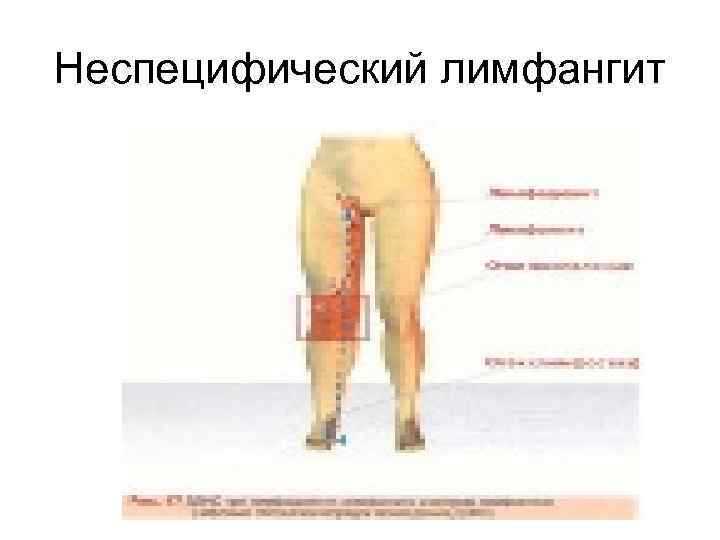

Неспецифический лимфангит